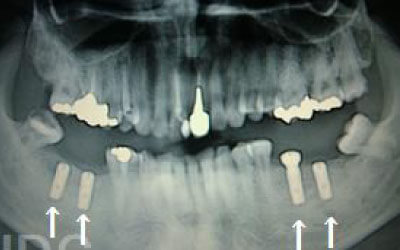

CTを使うことで、骨や歯の状態を3Dで確認でき、正確な距離測定も行えます。

骨の厚さや傾き、神経の位置などを事前にしっかりと計測することで、安全にインプラント治療を行うことができます。